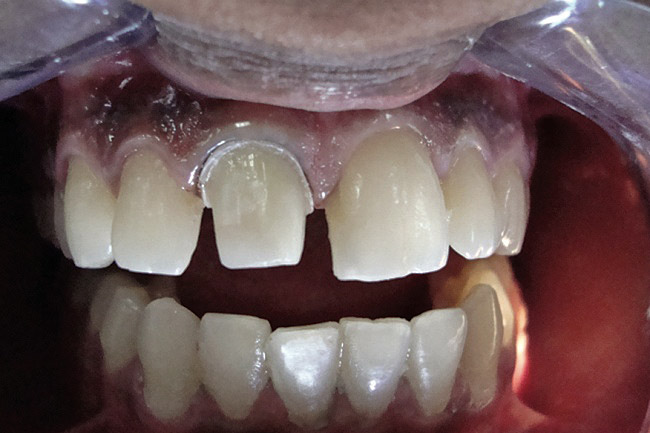

Figure 2  Caries extending cervically on upper right incisors.

Figure 2

Figure 3  Placement of rubber dam with application of cervical clamp on central incisor for extra retraction.

Figure 3

Figure 4  Final composite restorations with respect to upper right incisors.

Figure 4